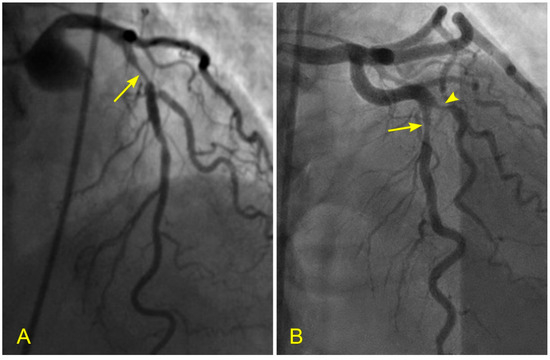

Figure 1.

The left anterior descending artery (LAD) in the anterior–posterior cranial view. There is a narrowing in the mid-segment of the LAD, distal to the origin of a moderate-size diagonal (arrow). The current angiography technique only shows the degree of stenosis without critical information on how the lesion was formed and how it will progress in the near or far future.